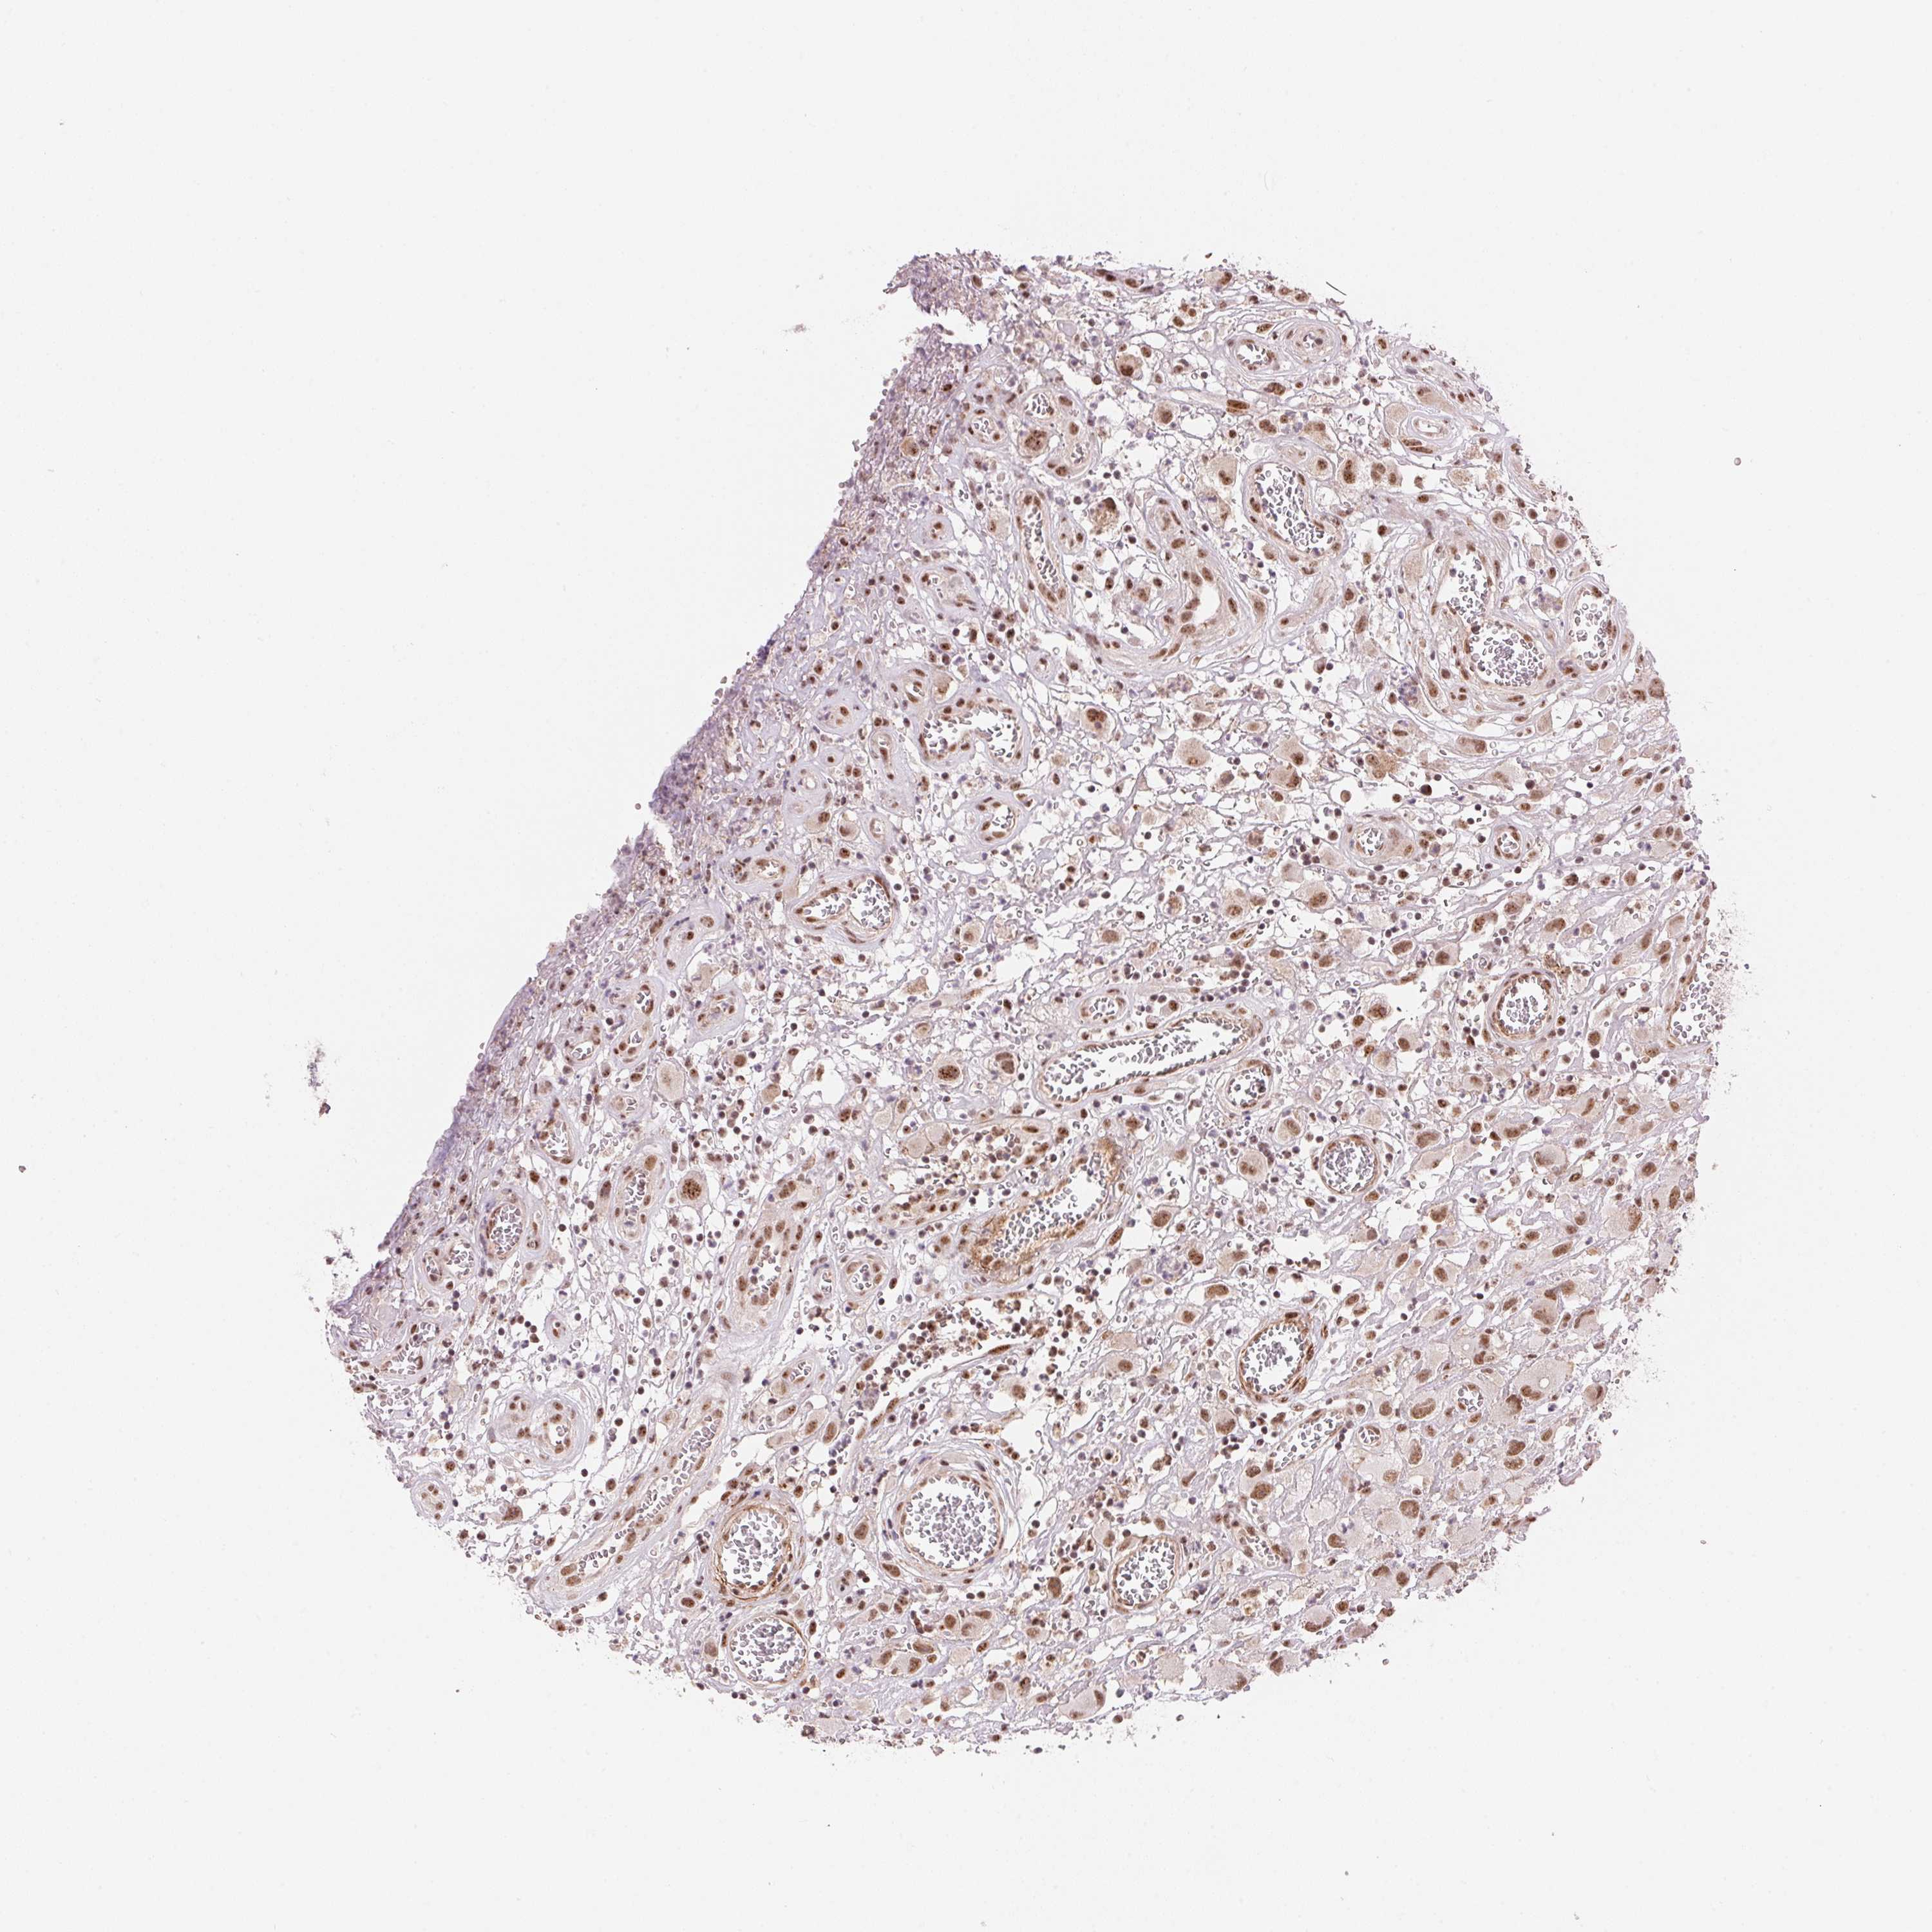

HEAD AND NECK CANCER - Protein expressioni

A mouse-over function shows sample information and annotation data. Click on an image to view it in a full screen mode. Samples can be filtered based on level of antibody staining by selecting one or several of the following categories: high, medium, low and not detected. The assay and annotation is described here.

Antibody stainingi

Antibody staining in the annotated cell types in the current human tissue is reported as not detected, low, medium, or high, based on conventional immunohistochemistry profiling in selected tissues. This score is based on the combination of the staining intensity and fraction of stained cells.

Each image is clickable and will lead to virtual microscopy that enables deeper exploration of all samples and also displays staining intensity scores, fraction scores and subcellular localization as well as patient and tissue information for each sample.

Antibody HPA056820

Antibody HPA063147

Staining

High

Medium

Low

Not detected

Intensity

Strong

Moderate

Weak

Negative

Quantity

>75%

75%-25%

<25%

None

Location

Nuclear

Cytoplasmic/membranous

Cytoplasmic/membranous,nuclear

Squamous cell carcinoma, NOS

Adenocarcinoma, NOS

Squamous cell carcinoma, metastatic, NOS